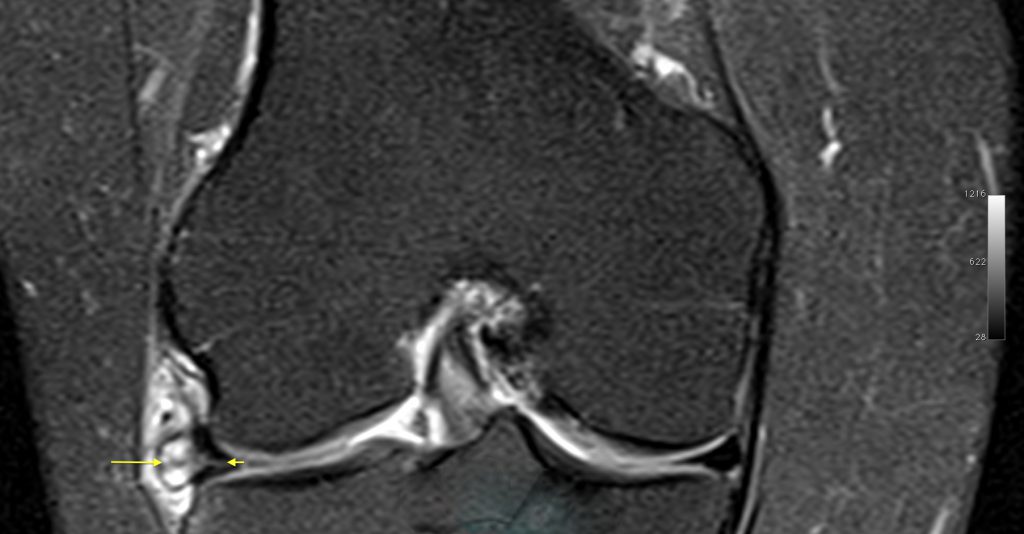

Lesão horizontal do menisco lateral e cisto parameniscal.

Corredora com dores na região do compartimento lateral do joelho e sensação de aumento de volume com formação de um nódulo palpável.

Realizado exame de ressonância magnética com identificação de lesão horizontal do menisco lateral (seta pequena) e formação cística parameniscal.